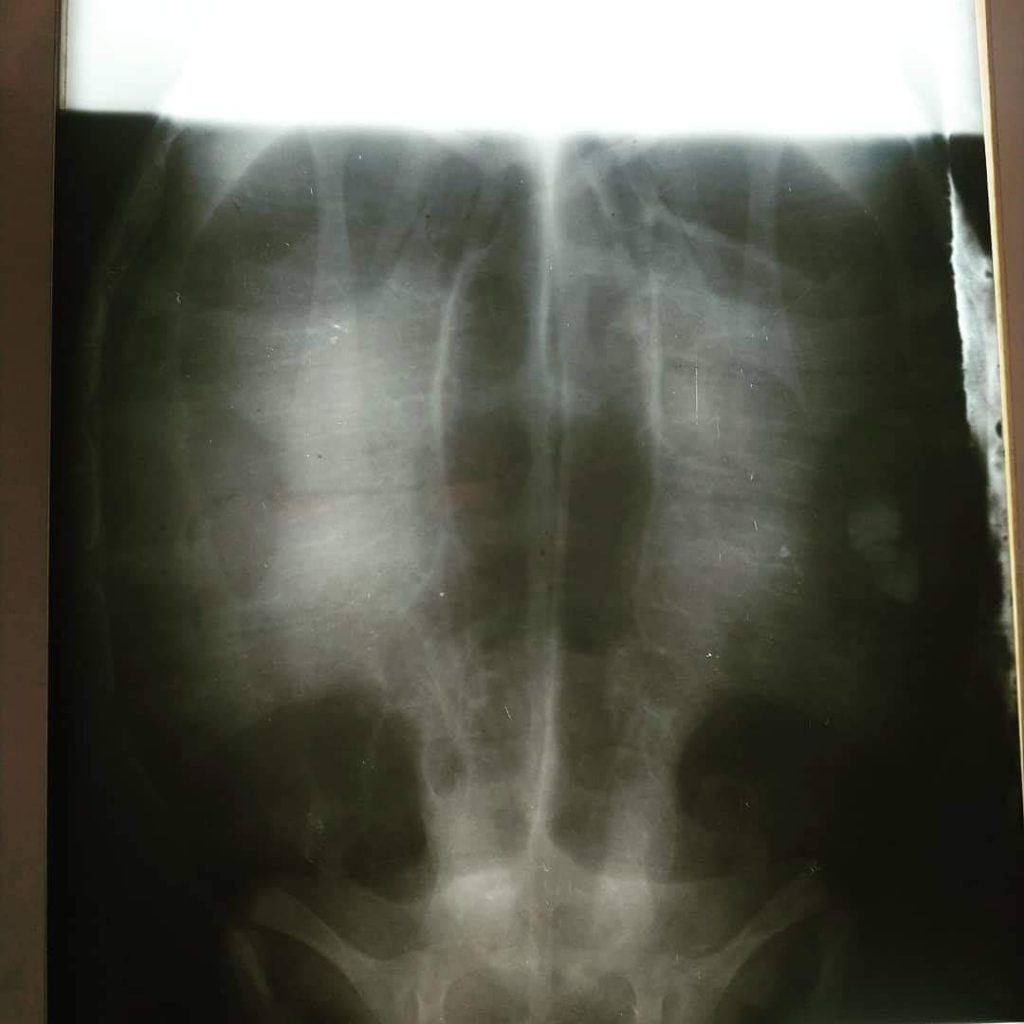

Isla Mujeres, Q. Roo, Lunes 10 de Agosto de 2020, poderycrítica.- Tras el reporte del varamiento de una tortuga Carey en el muelle del Hotel Mía, personal de la Tortugranja procedió a trasladar al quelonio a sus instalaciones, donde se le valoró para descartar heridas externas, posteriormente fue trasladada a la veterinaria Isla Mujeres A. C. donde se le realizó una serie de radiografías para asegurarse que no tenga algún cuerpo extraño.

Deline García Canto, directora de Tortugranja, explicó que, tras las radiografías en la veterinaria, con apoyo del grupo Tortuguero del Caribe A. C. el quelonio fue llevado a grupo Xcaret, el cual cuenta con equipo especializado en esta especie, para darle la debida atención, además de que la tortuga se encontraba en estado de desnutrición.